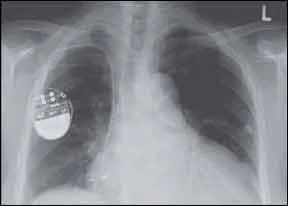

Hearing that a safety advisory has been issued for your implantable cardioverter-defibrillator (ICD) could be a frightening piece of news. But a recent study by Cleveland Clinic researchers suggests that an advisory from the Food and Drug Administration (FDA) is not associated with a significantly higher mortality rate than what would otherwise be expected in a patient with such a device. In the study, published in a recent issue of HeartRhythm, the mortality rate of people who whose devices were never the subject of an advisory was 52 percent over a period of 5.5 years, while the mortality rates of those whose devices were subject to a Class I advisory by the FDA was 54.1 percent, and 43.6 percent in patients with devices that received Class II advisories. The FDA divides medical devices into three classes: Class I and II devices are generally considered lower-risk, while Class III devices are higher risk and/or first-of-a-kind items.